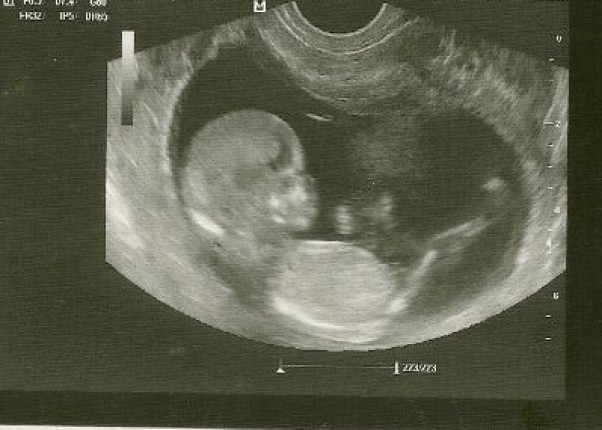

Tego dnia na wizycie lekarskiej w 17 tygodniu dowiedziałam się że będziemy mieli drugiego SYNKA.Moje przeczucie że będzie córcia,jednak się nie potwierdziło.Nasz synek też się na to nastawił,ale jak się dowiedział że będzie miał Braciszka to prawie do sufitu podskoczył z radości:) Stwierdził że przynajmniej nie będzie musiał rodzeństwa przymuszać do zabawy autami,robotami i klockami !Bardzo się cieszymy.Maleństwo rozwija się prawidłowo,mdłości już całkowicie mnie opuściły.Teraz mam czas i siły żeby wiedzę o płci naszego Skarba wykorzystać i rozpocząć kompletowanie wyprawki,bo garderoba naszego pierwszego 7 letniego już synka ogranicza się tylko do odzieży w "dużym" rozmiarze.Wszystko co maleńkie poszło już dawno w świat :)